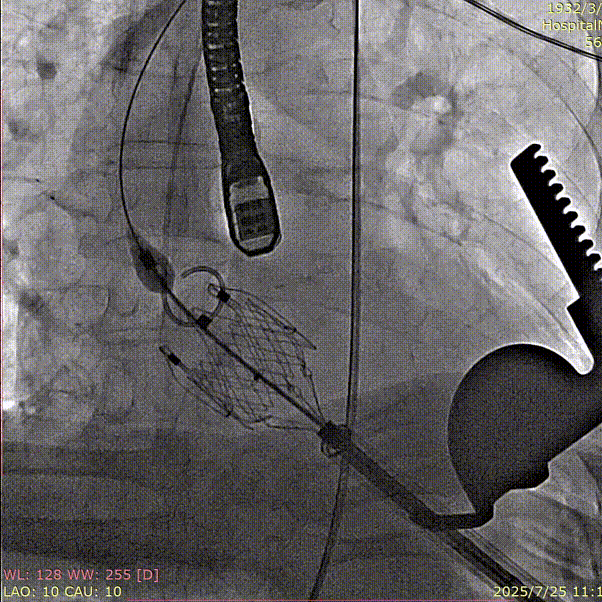

术中回顾及效果

手术过程顺利。术中夹持件入窦、定位一气呵成,瓣膜释放过程顺利、稳定,术中器械操作时间约10分钟。术后评估结果良好,瓣膜定位稳定,无瓣周漏,平均跨瓣压差为4mmHg,血流动力学表现良好。

术后患者顺利拔管,复查心脏超声左室射血分数55%,左室回缩至53mm,心脏功能较前明显改善,胸闷憋气症状消失,生活质量显著提升。

术前造影

夹持件顺利入窦

瓣膜释放

术后造影